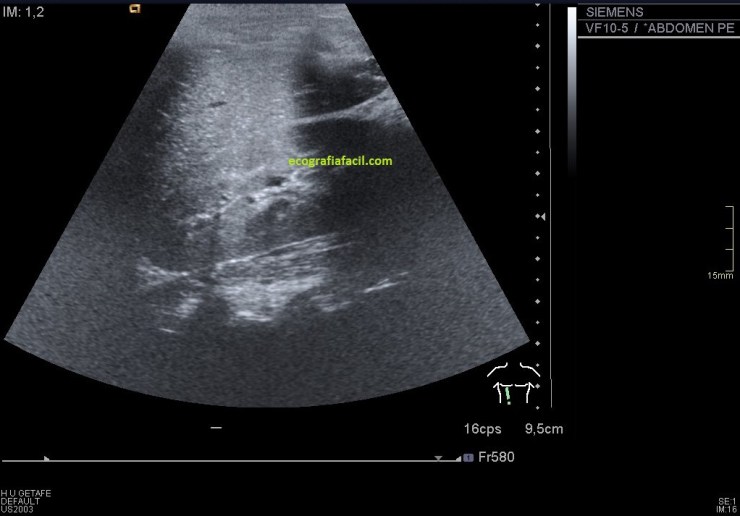

En el lado izquierdo no encontré el riñón en su localización normal, en decúbito prono, ya sabía que era ectópico, tuve que colocar a la paciente en decúbito supino y buscarlo pélvico, junto a la región umbilical se encuentra el RI, malrotado (posición anómala) de características normales morfológicamente hablando, observo polo inferior, pero no del todo, eso lo hago como puedes ver en la imagen 6.

Hago corte axial, la imagen no es limpia, es un riñón ectópico y malrotado, no vamos a conseguir una imagen perfecta…